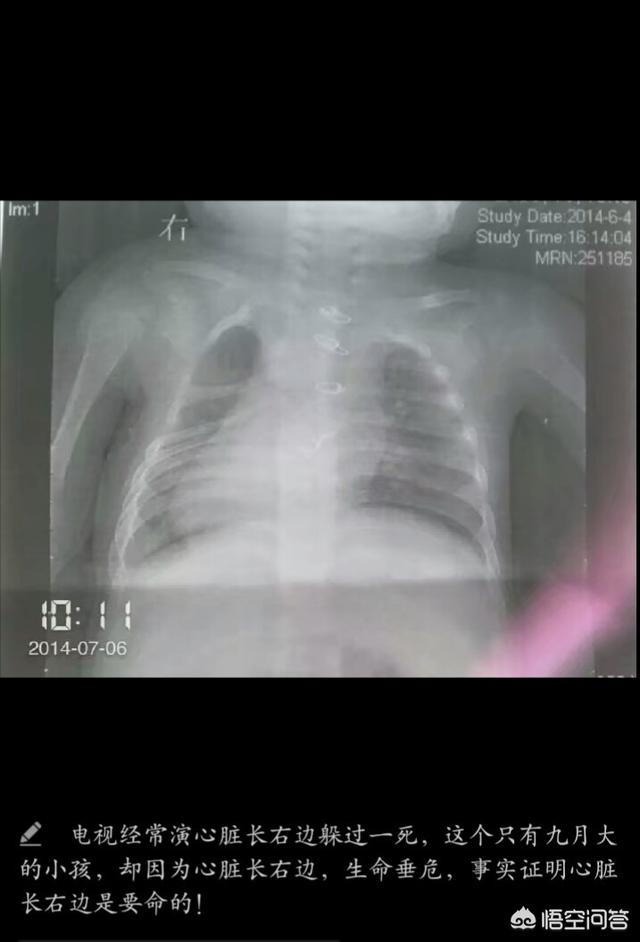

大概就是刚进临床第一次与死亡交战的时候吧!当时实习,我刚进临床,有个右位心的小孩,才八个多月大,长的特别好看,大眼睛,白白的,胖乎乎的,可是她带着的呼吸机提醒着我,这个小孩很虚弱,尽管已经做过一次手术,家里人也尽全力去医治,可是孩子太小已经经不起二次手术的折腾了,她还那么小,还没好好看看这世界,却经历了那么多的磨难,那时候就觉得,爸妈给我一个健康的身体,让我健康快乐成长是件多么幸福的事情。